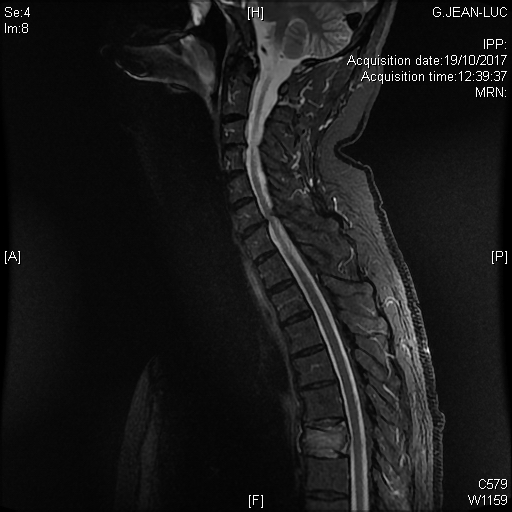

Multiples lésions vertébrales rachidiennes avec compression médullaire et épidurite à l'étage T5, dans le cadre d'un cancer pulmonaire, en séquence T2 STIR